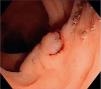

En las figuras 1, 2 y 3 se observan muestras de los pólipos detectados con las técnicas colonoscópicas i-SCAN, subacuática y Endocuff.